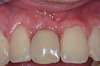

La prothèse est alors posée immédiatement après l'implant.